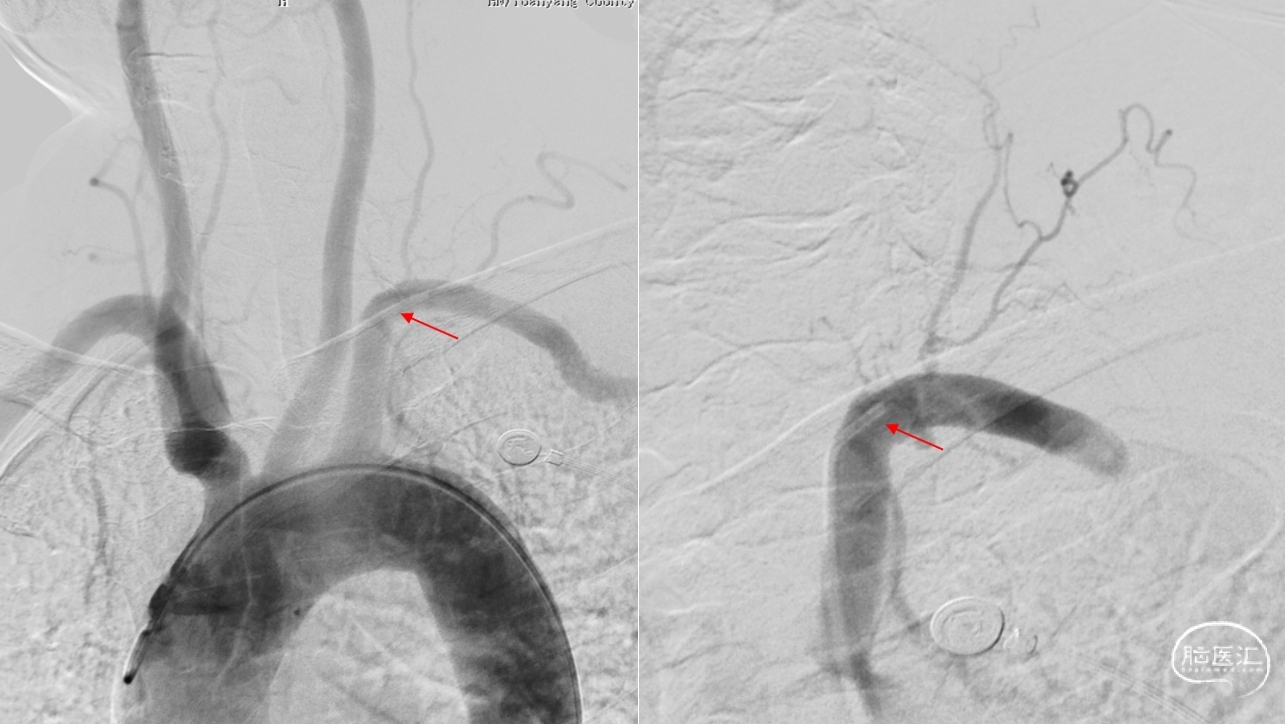

外院闭塞开通未成功(2023-7-5)

闭塞开通术(股动脉入路)

颈升动脉与椎动脉V2/V3段沟通

枕动脉与椎动脉V3段沟通,左侧后交通开放

右侧后交通开放

右侧劣势椎动脉V4段纤细